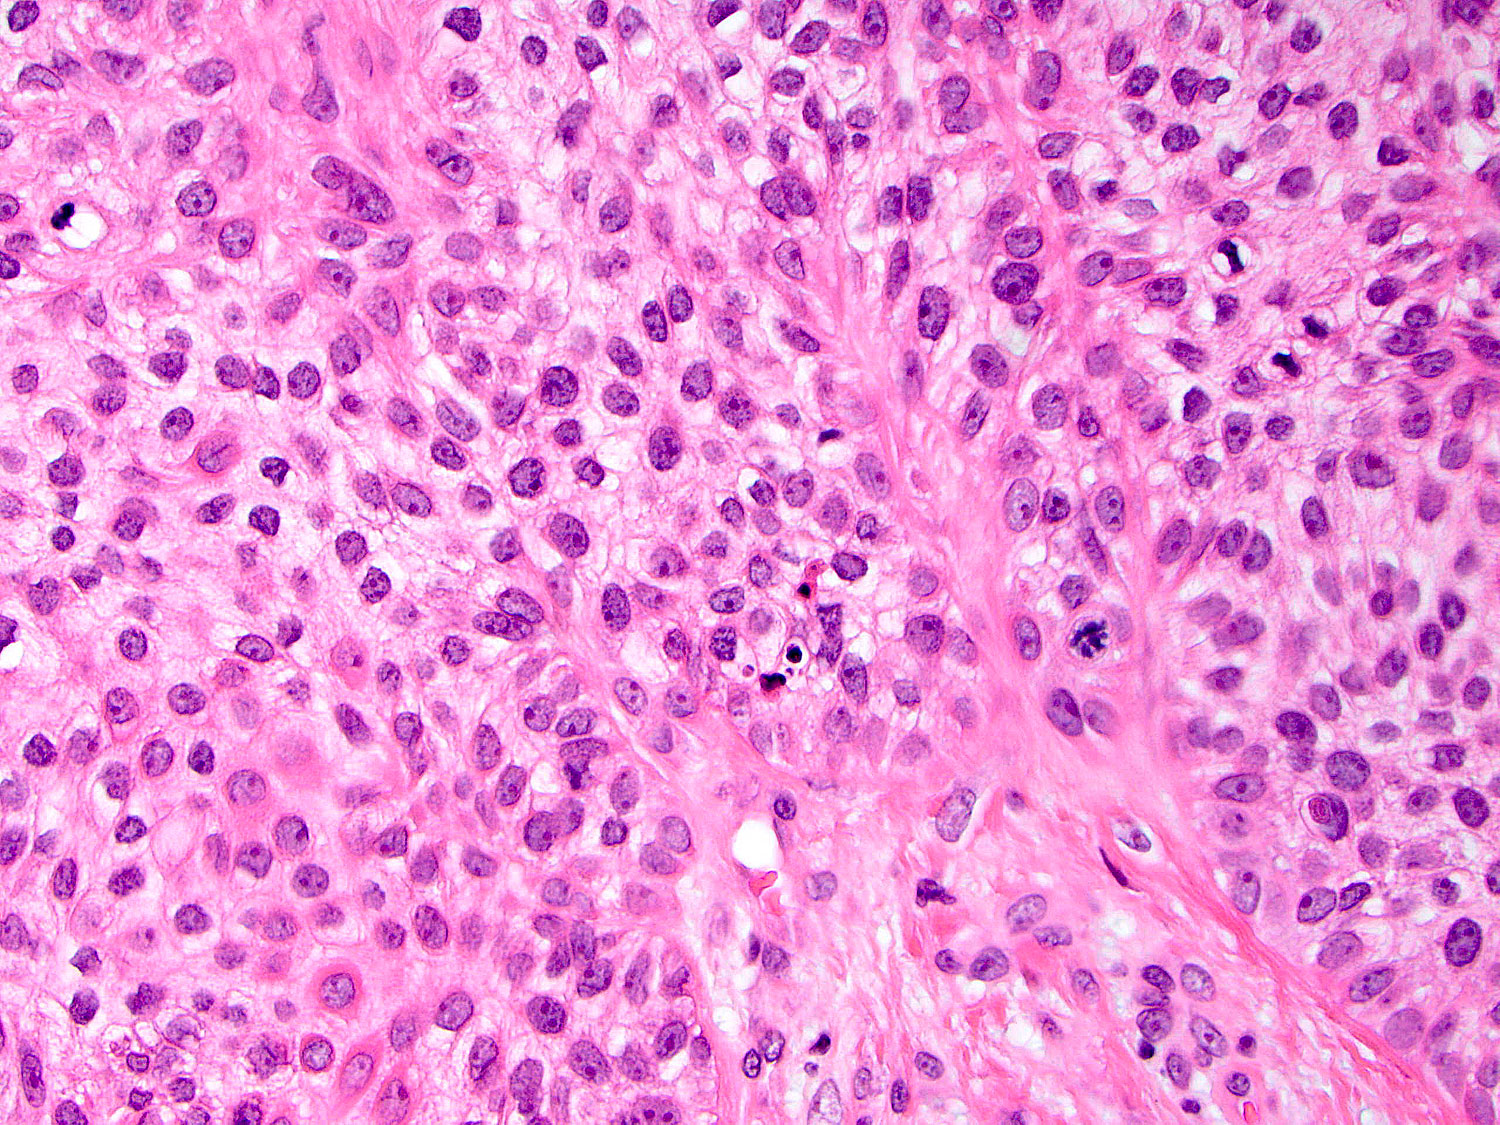

H&E staining (40x objective)